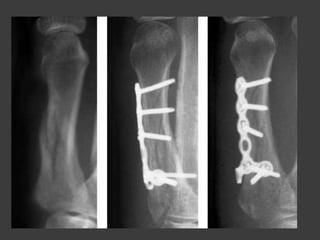

Fx de la cabeza de los

metacarpianos

Fijación de fragmento grandes -

anterogrado

Fijación de fragmentos

pequeños - retrogrado

Metodos de reducción

Transversales

Oblicua

Conminuta